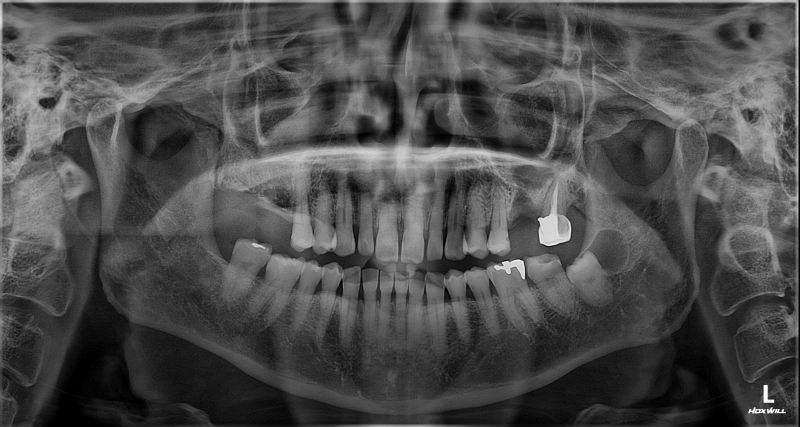

촬영일시: 2026.04.10